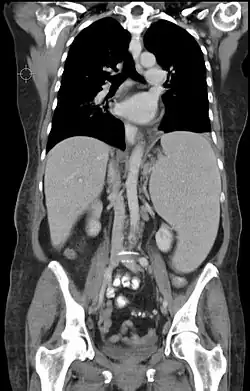

Die Diagnose wird in der Regel durch Ultraschall, Kernspintomographie und/oder Computertomografie gestellt.[3] Neben einer Messung der Milzgröße erlauben diese Untersuchungstechniken auch eine bildliche Darstellung der inneren Struktur der Milz und können Hinweise über die zugrunde liegende Erkrankung liefern.[3] Bei der körperlichen Untersuchung kann sich neben einem lokalen Druckschmerz unterhalb des linken Rippenbogens eine vergrößert tastbare Milz darstellen.[4] Splenomegalien können zu einer Überdehnung des Milzgewebes und somit zu einer spontanen Milzruptur führen. Klinisch zeigen sich hier in Abhängigkeit vom Blutungsausmaß ein hämorrhagischer Schock sowie Schmerzen im linken Oberbauch. Die Diagnose hier wird ebenfalls durch Ultraschall oder Computertomografie gestellt.[5]